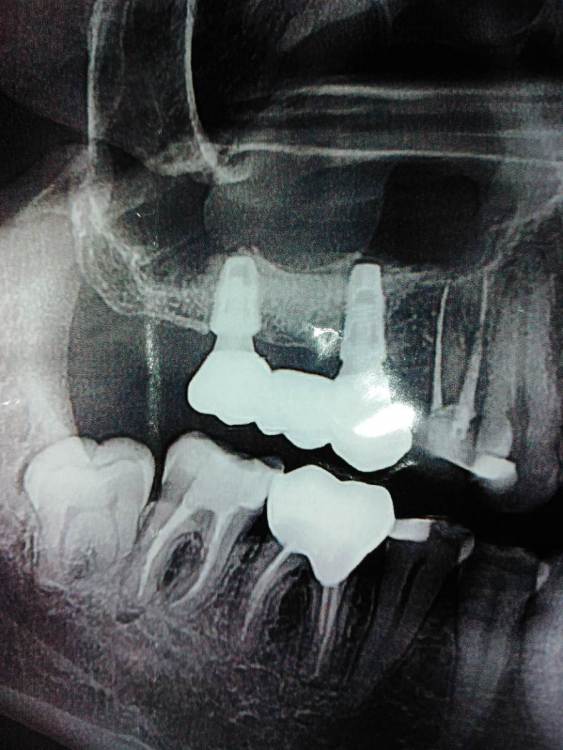

St. Опубликовано 29 июля, 2021 Поделиться Опубликовано 29 июля, 2021 Добрый день. По снимку все хорошо, показаний к перелечиванию каналов нет 1 1 Ссылка на комментарий

еатегsffhgj Опубликовано 2 августа, 2021 Автор Поделиться Опубликовано 2 августа, 2021 подскажите пожалуйста,нет ли воспаления на верхушках корней? Ссылка на комментарий

еатегsffhgj Опубликовано 29 сентября, 2021 Автор Поделиться Опубликовано 29 сентября, 2021 мне перелечили зуб с микроскопом. заложил врач в каналы кальций. на фото уже с кальцием. далее начал болеть зуб весь при прикосновении,а в покое просто ныть. с каждым днем болит все больше. мой врач в отъезде. через администраторов передала,что надо терпеть. 5 дней,я уже кроме зуба ни о чем думать не могу. вчера пошел к хирургу. были мнения у врачей,что боли могут быть из за 8 зуба. хирург все прощупал и сказал,что дело не в 8 зубе. разрезал десну и где то просверлил отверстие. боль в этот момент была на ту,которая у меня постоянно,только гораздо сильнее. прописал антибиотики,сказал,что должно стать легче. но,легче не становится. так же ноет зуб без обезболивающего,и сильно болит при надкусывании. подскажите пожалуйста, что мне делать? как успокоить эту боль хотя бы? неужели нет никаких средств у врачей? много раз делали кальций,и всегда это только помогало,а здесь просто невозможно. мне надо уезжать через неделю, подскажите,в каком направлении мне двигаться? или ,вообще удалить этот зуб уже? нет сил больше Ссылка на комментарий